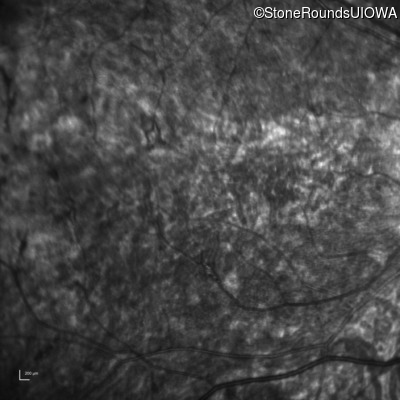

Infrared Fundus Photograph - Right - 5/200

Exemplar